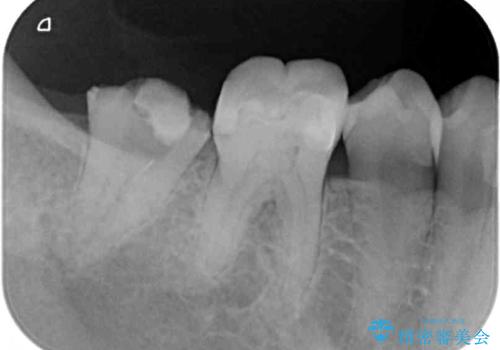

- 奥歯の詰め物が取れ、近医で再装着してもらったものの、すぐに脱落してしまったとのことで来院された患者様です。

既に神経は失活していましたが根管治療はされておらず、むし歯が大きかったためか、歯全体が手前に動いてしまっていました。

まずは根管治療を行い、その後アンカースクリューを用いて歯を適切な位置まで後方移動させた上で、セラミッククラウンによる補綴治療を行うこととしました。